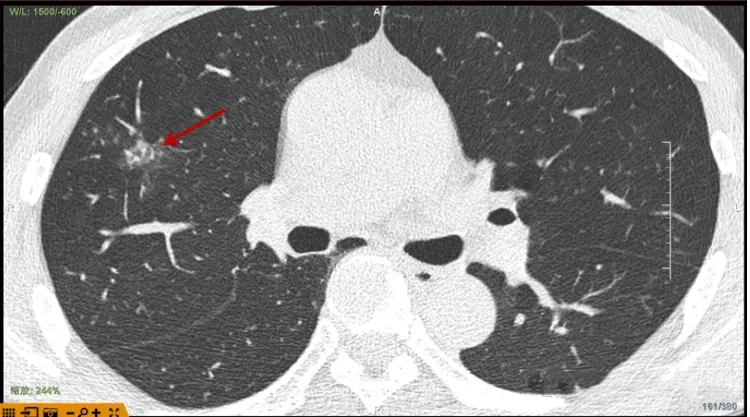

术前CT

52岁的尹先生在年度体检中发现右上肺出现一个周围型肺结节,这让有长期吸烟史和肺癌家族史的他倍感忧虑。面对医生“手术切除”的建议,尹先生顾虑重重:传统手术创伤大、恢复慢。经多方咨询,他了解到一项名为“无痕肺结节肺癌消融术”的新技术,最终在局麻+全麻复合麻醉下,一小时顺利完成手术,术后无发热、咯血、胸痛或气胸等不适,次日平安出院。这项融合多学科高精尖技术的微创手术,正为无数像尹先生这样的肺结节患者带来新希望。